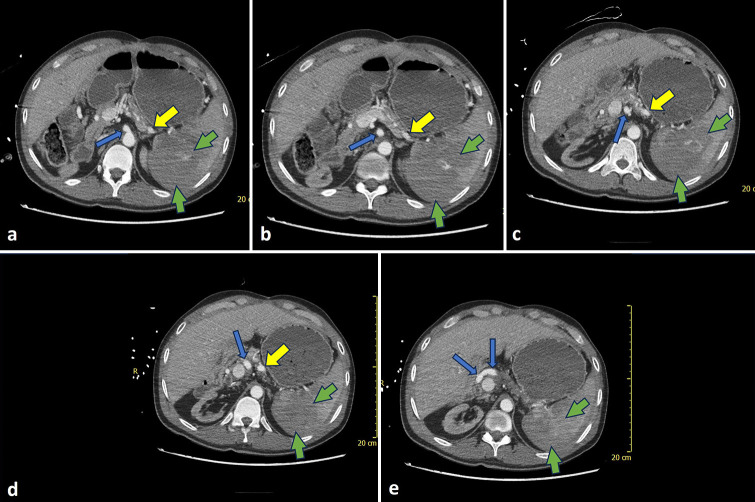

The spleen is a highly vascular organ susceptible to injury in blunt abdominal trauma, often leading to massive blood loss. Splenic artery embolization (SAE) has been shown to be a safe and effective nonoperative approach in cases of hemodynamically stable patients with blunt splenic trauma. SAE can be performed proximally or distally, with both approaches demonstrating similar clinical efficacy. This case report describes emergent splenic embolization for acute abdominal trauma in a liver transplant recipient. However, due to the presence of prior splenic artery ligation, a uniquely alternative route through the gastroepiploic artery was used to gain access to the spleen for embolization.

Abstract Image